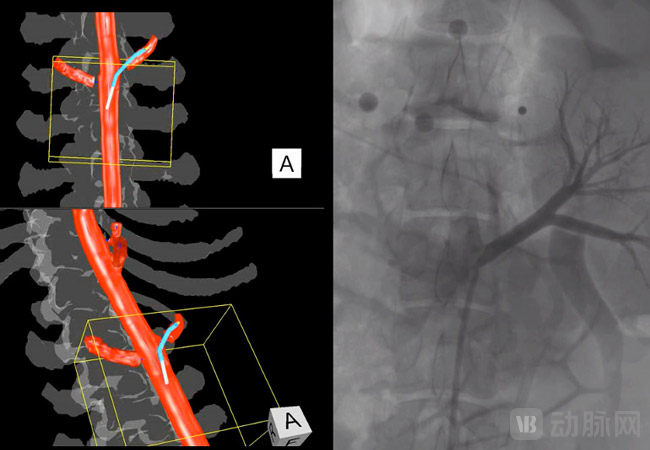

IOPS技术摈弃了传统的DSA导航,将术前CT动脉造影图像转化成3D彩色图像,再将3D图像呈现在手术室的显示屏上。

IOPS®系统采用电磁定位技术,在操作台下方放置一台电磁场发生器,配备磁场定位传感器的手术设备,磁场会使传感器产生电信号,再耦合影像图像和电信号,即可得出穿刺针运动轨迹。为了减少误差, IOPS®系统在患者腰部放置定位校准贴片。

根据Centerline Biomedical官网介绍,使用IOPS®系统进行穿刺所需时间仅为传统2D导航的53.4%。并且IOPS®系统采用3D彩色图像,实时跟踪穿刺针,优于传统的2D灰色图像。

IOPS®系统与传统2D图像对比 图源官网